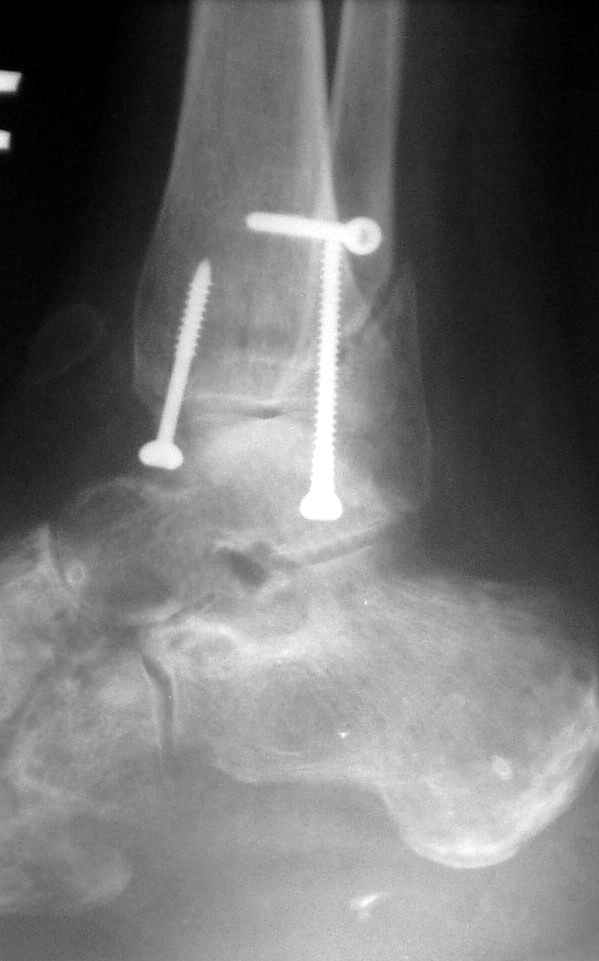

Ниже рентгенограммы

До операции 28 июля

Операция 29 июля

Через месяц

Боковой через месяц

15 ноября прямой

15 ноября боковой

15 ноября трехчетвертной

12 января прямой

12 января боковой

12 января трехчетвертной

Риторический вопрос - в каком руководстве рекомендован такой способ остеосинтеза наружной лодыжки?

Очевидно, такой результат операции был запрограммирован. При невосстановленной длине и практически нефиксированной малоберцовой кости (этот кортикальный винт - как карандаш в стакане), при неустраненном подвывихе, невправленной и тоже нефиксированной внутренней лодыжке нет стабильной вилки сустава. Если такую операцию сделать даже сразу, а не через 4 месяца, то результат ожидаем

тот же.

Вообще говоря, такое повреждение вполне успешно можно лечить без операции - если 6 недель подержать в гипсовом "сапожке" с хорошо устраненным подвывихом. Вероятное несращение внутренней лодыжки не обязательно компрометирует результат.

Ну а уж если выбран остеосинтез - нначать надо было с репозиции малоберцовой кости с точным восстановлением длины, с фиксацией треть-трубчатой пластиной по задней поверхности. Позиционный винт

избыточен - повреждение практически подсиндесмозное. А если бы

действительно было повреждение синдесмоза - в 4 месяца позиционный винт - не решение. Внутренню лодыжку такую - надо было бы спицами и проволочной петлей. Извините за эти банальности.

Вариант с артродезом уже обсудили. Хотя, после увиденых снимков, пессимизм насчет восстановительной операции у меня, например, несколько уменьшился. Особенного уж какого-то остеопороза не видно даже на январских снимках. Можно черед мини-доступы убрать винты, аппаратом вправить малоберцовую кость, устранить подвывих стопы. Ну а дальше фиксировать малоберцовую пластиной сзади. А может, и напряженной Y-спицей попробовать - Анатолий Федорович, как Вы полагаете? Внутреннюю - то, что осталось, если уже не получится сделать спицами и проволокой, то что-то типа пластики дельтовидной связки. А может, и не трогать ее вовсе... В общем, выбор непростой,

много факторов надо взвесить.